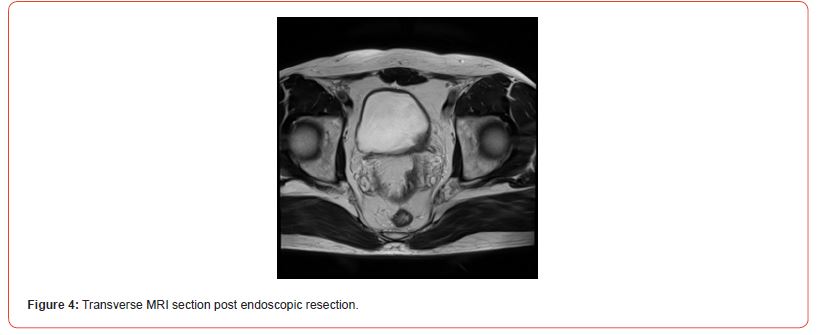

Immunostaining of the tumor cells showed heterogeneous positivity for keratin AE1E3. This positivity was lower in terms of intensity compared to the adjacent normal urothelial lining. There was no positivity for anti-p63 antibody. The tumor cells were focally positive for anti- Desmin and SMA antibodies. The proliferation index, evaluated using anti-Ki67 antibody, was estimated to be between 5 and 10% depending on the analyzed areas. There was strong and diffuse immunostaining for anti- ALK antibody. Fluorescence In Situ Hybridization (FISH) analysis showed rearrangement of the ALK gene in 84% of cells (Figure 3). The microscopic and immunohistochemical examinations are suggestive of IMT or pseudosarcomatous IMT. Microsatellite instability testing was performed. The MLH1, PMS2, MSH2, and MSH6 antibodies showed nuclear positivity, which is not suggestive of microsatellite instability for this tumor. A postoperative pelvic MRI (Figures 4&5) showed a heterogeneous enhancing lesion on the left postero-lateral wall of the bladder, measuring 26 x 22 x 14 mm, near the uretero-vesical junction, without extravesical extension.